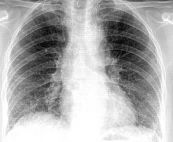

Viêm phế quản cấp tính có thể chịu trách nhiệm cho ho khan và đờm, đôi khi đi kèm với viêm đường hô hấp. Bài viết này sẽ nói rõ hơn về hội chứng Viêm phế quản cấp trên x quang chuẩn. Mời các bạn tham khảo!

Các triệu chứng phổ biến nhất của COPD là khó thở, sản xuất đờm quá mức, và ho mãn tính. Hình ảnh trên phim chụp x quang ngực gợi ý chẩn đoán bệnh phổi tắc nghẽn mạn tính (COPD). Để hiểu rõ về hội chứng này mời các bạn cùng tham khảo bài viết Bệnh phổi tắc nghẽn mạn tính (COPD) trên x quang.